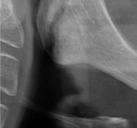

En la ortopantomografía se aprecia una dentición permanente a falta de la erupción de los 2os y 3 os molares, así como una asimetría ósea con rama y cóndilo mandibular izquierdo menos desarrollado (figura 9), causante de la asimetría facial descrita anteriormente.

El estudio cefalométrico (figura 10) revela una Clase II esquelética por hipoplasia mandibular, patrón braquifacial e incisivos superiores muy protruidos (14,9 mm) y

vestibulizados (52º), e inferiores lingualizados (16 º). El perfil es extremadamente convexo.